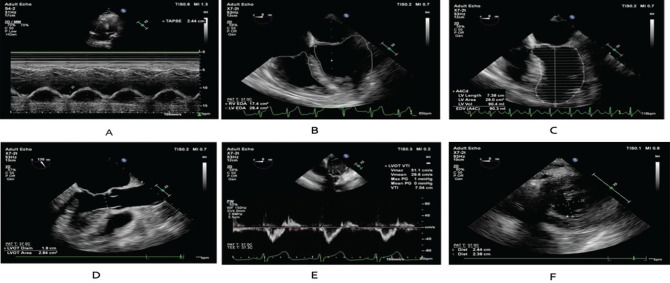

Methods: This prospective study included 30 moderate-to-severe C-ARDS patients who were treated with PP in the first 48 h of invasive mechanical ventilation support. It was evaluated with TEE three times: before PP (T0f), the first hour of PP (T1), and the first hour of returning to the supine position (T0 + 24 h) (T2) after 23 hours of PP treatment. RV end-diastolic area/left ventricular (LV) end-diastolic area (RVEDA/LVEDA), tricuspid annular plane systolic excursion (TAPSE) and LV end-systolic eccentricity index were preferred RV evaluations as primary outcomes. Pulmonary effects of PP were evaluated as a secondary outcome, including PaO2/FiO2, driving pressure (dP), static compliance (Cstat), mechanical ventilation parameters, and their association with 28-day survival. Tissue DO2 was examined as a secondary outcome, and it was calculated using the measured cardiac output through TEE.

Results: With the cardiopulmonary effect of PP, the decrease in RVEDA/LVEDA, the increase in TAPSE, PaO2/FiO2, and Cstat, and the decrease in dP were statistically significant (P < 0.05). The Cstat value associated with 28-day survival showed decreased mortality for each unit increase. The Cstat cut-off value, which was statistically significant for survival, was 37.